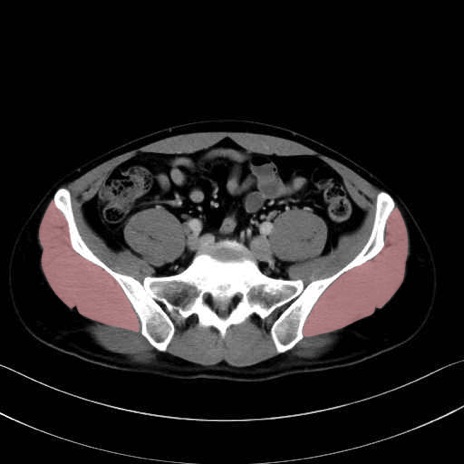

中殿筋 (Gluteus medius)